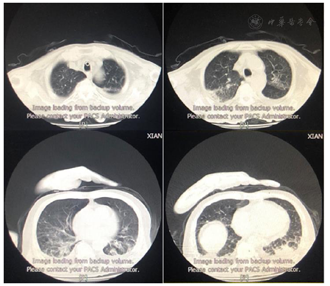

患者医学影像学检查如图1,图2,图3,图4,图5,图6,图7,图8所示,实验室检查结果如图9,图10,图11所示。

2021年3月24日患者出现顽固性低氧血症,血D2-二聚体:12810.00 ng/ml,CTPA显示肺动脉分支栓塞,双下肢静脉彩超:双下肢静脉血栓形成。加用抗凝治疗,调整康复治疗方案:(1)吸氧,监测血氧饱和度下完成康复训练项目;(2)依据患者耐受调整康复训练项目;(3)加强床旁呼吸功能训练。经上述治疗后,患者血氧饱和度有所上升,痰量有所下降,吸痰次数减少。结合患者肺部状况改善的情况给予佩戴说话瓣膜,约4 h/d,同时行语音训练,患者发音逐渐较前稍清晰,痰液可经口咳出,但仍有大量痰液瘀滞于咽部,需要辅助清除,血氧饱和度为85%~95%。2021年5月11日突发寒战、高热、皮肤花斑、咳嗽、大量咳痰,氧饱和度下降至60%。血象、感染相关指标升高;胸部CT:双肺炎症较前加重,双肺间质性病变;支气管三维重建:气管、支气管内分泌物,下叶各段支气管开口显示不清;痰培养:铜绿假单胞菌。经美罗培南抗感染治疗,并加强化痰、气管管理,加强翻身、拍背、排痰宣教后,患者未有发热,咳嗽、咳痰较前好转、感染指标正常;复查支气管三维重建:气道结构通畅;指脉氧饱和度:88%~97%。